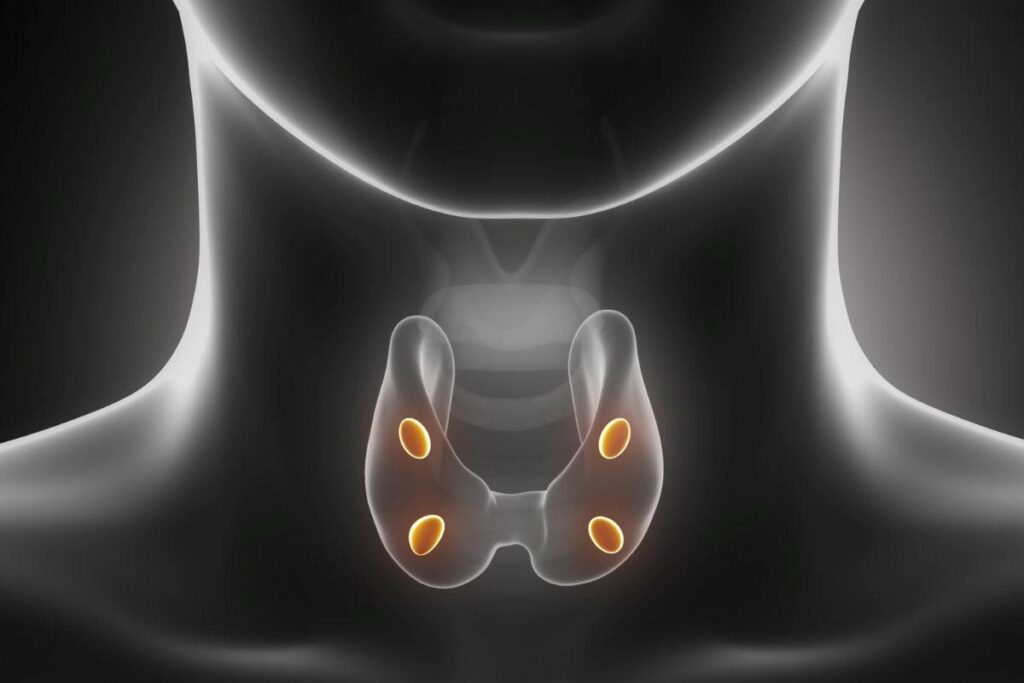

Ambas envolvem o funcionamento das glândulas paratireoides, presentes em número de quatro e próximas à tireoide, que são responsáveis pela produção do paratormônio (PTH), hormônio essencial para o equilíbrio do cálcio, do fósforo e da saúde óssea.

Qual é a função das paratireoides no organismo?

As paratireoides são pequenas glândulas localizadas atrás da tireoide e têm como principal função regular os níveis de cálcio no sangue por meio da produção do PTH.

A liberação do PTH ocorre, principalmente, em resposta à queda do cálcio no sangue. Quando os níveis de cálcio diminuem, sensores presentes nas paratireoides detectam essa alteração e estimulam imediatamente a liberação do hormônio. Em contrapartida, quando o cálcio está adequado ou elevado, a produção de PTH é reduzida, mantendo o equilíbrio metabólico.